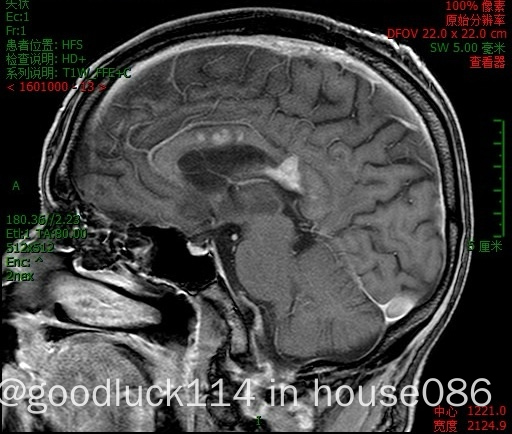

高龄取不了病理,医院做不了pet-ct,做了头颅ct和mri,发现颅内占位性病变,怀疑原发或转移,但胸部ct腹部ct和肿瘤标志物都没有明显异常,也没有除神经系统外其他系统的症状,mri增强结果不像是胶质瘤,高度怀疑是原发性中枢淋巴瘤。